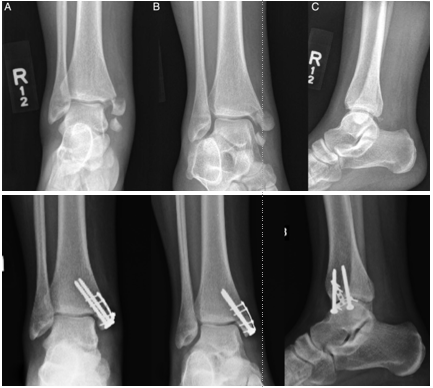

一例内踝骨折,空心钉 or钢板?或者二者?